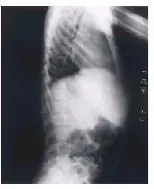

Alteraciones radiológicas: cara y cráneo fontanelas permeables, huesos wormianos con fracturas, hipoplasia malar y mandibular, dientes apiñados; hipoplasia clavicular en el tórax, costillas ahusadas; largos identaciones en los huesos, corticales delgadas, metáfisis anchas, coxa valga, coxa plana, genu valgum; en las falanges acro-osteolisis progresiva de las falanges distales; y otros signos como osteoporosis, escoliosis, cuerpos vertebrales en forma de boca de pescado, luxación de cadera, falta de unión de fracturas y pérdida de tejidos blandos.

1- Rayos X de tórax (vista anteroposterior). Osteólisis total de ambas clavículas y de las primeras costillas. Osteólisis parcial de las segundas y terceras costillas.

2- Rayos X de columna lumbosacra (vista lateral). Persistencia de la escotadura en cara anterior de las vértebras dorsales (vértebras en fishmouth). Espondilolistesis de la quinta vértebra lumbar sobre la primera sacra.